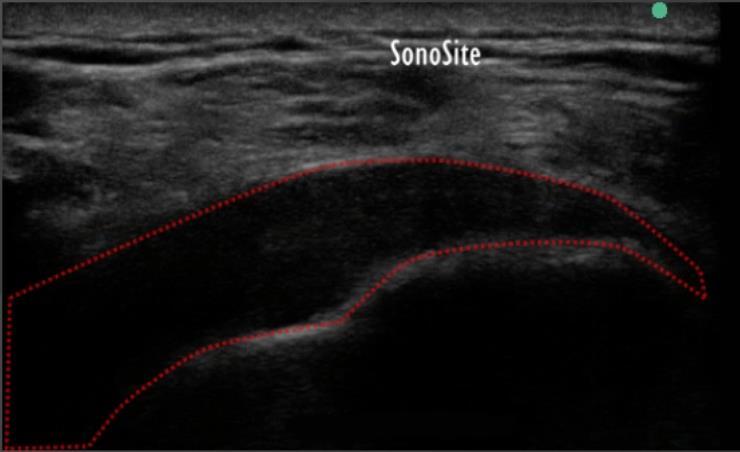

肩部弥散性肌腱病 1 图像